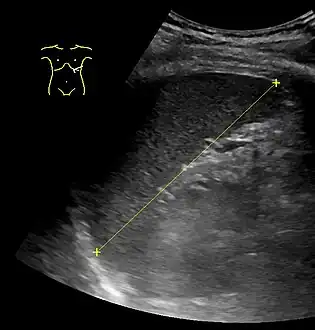

The spleen, in healthy adult humans, is approximately 7 to 14 centimetres (3 to 5+1⁄2 in) in length.

An easy way to remember the anatomy of the spleen is the 1×3×5×7×9×10×11 rule. The spleen is 1 by 3 by 5 inches (3 by 8 by 13 cm), weighs approximately 7 oz (200 g), and lies between the 9th and 11th ribs on the left-hand side and along the axis of the 10th rib. The weight varies between 1 oz (28 g) and 8 oz (230 g) (standard reference range),[12] correlating mainly to height, body weight and degree of acute congestion but not to sex or age.[13]

Maximum length of spleen on abdominal ultrasonography